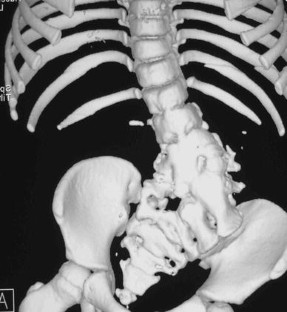

Fig. 3